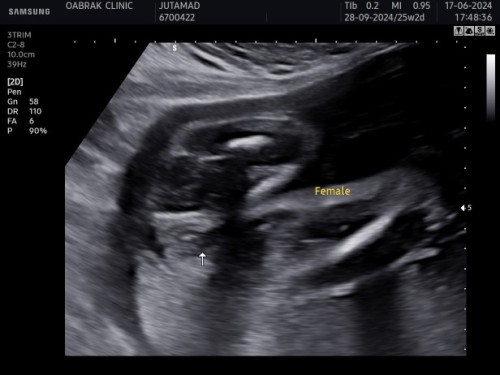

รบกวนแม่ๆช่วยดูหน่อยค่า หมอบอกว่าน้องเป็นผู้หญิง แต่แม่แอบอ่านเจอหลายๆท่านที่ซาวเป็นผู้หญิงพอคลอดมาจู๋โผล่ แม่เลยแอบกังวลนิดหน่อยค่า แต่จริงๆแล้วเพศอะไรก็ได้แค่อยากมั่นใจจะได้เตรียมของค่า

ถ้ายังไม่เห็นจู๋น้องแหลมๆคิดว่าน่าจะเป็น ผญ นะคะ เหมือนน้องอ้าขาด้วย